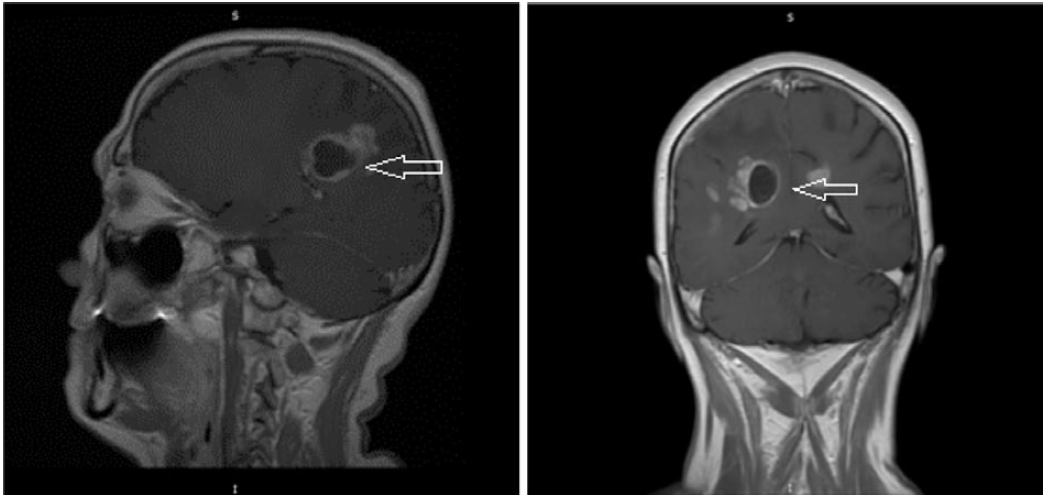

Больная С., 60 лет, считает себя больной на протяжении 3 мес, когда заметила опухолевидное образование в области малой половой губы с изъязвлением. В менопаузе 16 лет. Обратилась за медицинской помощью в онкодиспансер. При цитологическом исследовании отпечатка с опухоли – плоскоклеточный ороговевающий рак. По данным спиральной компьютерной томографии (КТ) органов грудной полости и магнитно-резонансной томографии (МРТ) брюшной полости и малого таза признаков очаговой патологии не выявлено. В январе 2018 г. выполнено оперативное вмешательство в объеме вульвэктомии. При гистологическом исследовании – в подэпителиальных слоях участки крауроза с ростом плоскоклеточного ороговевающего рака. В январе 2020 г. появились слабость в левой верхней и нижней конечности, шаткость при ходьбе, общая слабость. По поводу этого она обратилась к неврологу по месту жительства. При МРТ ГМ с контрастным усилением от 04.02.2020 – в затылочной доле справа, паравентрикулярно, с выраженным перифокальным отеком, определяется кистозно-солидное образование с неровным контуром размером 29×33×65 мм без клинически значимого «масс-эффекта». Срединные структуры не смещены (рис. 1, 2).

Рис. 1. Больная С., 60 лет. На серии аксиальных T1, T2-взвешенных и постконтрастных томограмм ГМ в затылочной доле паравентрикулярно, с выраженным перифокальным отеком, справа определяется кистозно-солидное образование с неровным контуром размером 29×33×65 мм, без клинически значимого «масс-эффекта».

Fig. 1. Patient S., 60 years old. On the series of axial T1 images, T2-weighted postcontrast tomograms images of the brain in the occipital lobe paraventricular, with intensive perifocal edema, to the right is defined cystic-solid formation with rough edges which size is 29×33×65 mm, without clinically significant mass-effect.